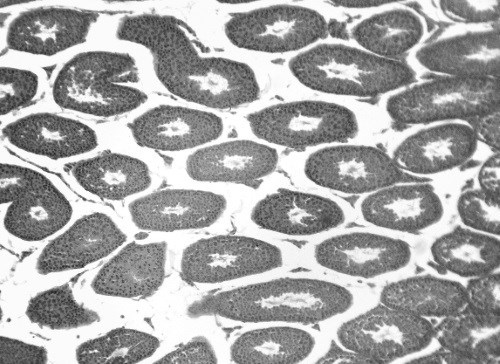

После активации половые железы начинают вырабатывать собственные гормоны, способствующие созреванию половых органов и развитию вторичных половых признаков, которые делают нас либо мужчинами, либо женщинами. ![]() Большая метаморфоза Мы превращаемся из ребенка во взрослого благодаря важнейшему физиологическому процессу – половому созреванию. Под чутким руководством гормонов оно вызывает физические и эмоциональные изменения, которые останутся с нами на всю жизнь. Период пубертата олицетворяет конец детства и начало нового приключения, полного проб и ошибок, радости и удовольствий. Активаторы полового созревания На протяжении многих веков точные факторы, запускающие процесс полового созревания, оставались загадкой. Современные исследования указывают на то, что набор веса и жировой массы может быть первым этапом пубертата. Это связано с теорией о том, что наше тело сначала должно достичь определенного базового веса. Тогда в организме будет достаточно ресурсов для дальнейших изменений. У мальчиков этот весовой порог значительно выше, поэтому их пубертатный период начинается немного позже. Считается, что как только лептин, вырабатываемый жировой тканью гормон (см. «Вторичные эндокринные органы» на стр. 235–236), достигает определенного уровня, гипоталамус активирует гипофиз и начинает выплескивать гонадотропин-рилизинг-гормон. Это запускает выброс лютеинизирующего гормона (ЛГ) и фолликулостимулирующего гормона (ФСГ) в кровь. Главной целью данных гормонов являются яички и яичники. ![]() Это молекулярная 3D-структура ФСГ – гонадотропного гормона, чьи клетки-мишени – наши половые железы. Скачок роста Пубертатный период вызывает быстрый скачок в развитии, обусловленный выработкой гормонов роста из передней доли гипофиза. Гормон роста, или соматотропный гормон, стимулирует печень к выработке гормона – инсулиноподобного фактора роста 1 (ИФГ-1). Он запускает рост мышц и хрящей на эпифизарной пластинке длинных костей. В период полового созревания все процессы катализируются эстрогеном, который выделяется у обоих полов (но больше, конечно, у девочек) и способствует выработке ИФГ-1. Это, кстати, объясняет, почему в пубертатном периоде девочки растут быстрее мальчиков. Хрящевые клетки с эпифизарной пластинки вступают в стадию быстрого деления, выталкивая более старые клетки в центр. Эти клетки сплющиваются и затвердевают, постепенно вытягивая длинные кости на целых 7–10 см каждый год. Внезапно выросшие конечности смещают центр равновесия в организме и мозг должен успеть приспособиться, поэтому подростки бывают неуклюжи. Физические изменения Большая часть изменений, возникающих в период полового созревания, обусловлена полом. Но есть ряд общих изменений: рост волос на лобке и в подмышечных впадинах, а также появление акне из-за гормональной стимуляции сальных желез. Эти железы начинают выделять слишком много кожного сала, и им требуется какое-то время для того, чтобы найти баланс. ![]() Этапы взросления – от младенчества к старости – сопряжены с рядом изменений, самые важные из которых происходят в период полового созревания. ![]() По мере взросления наш организм претерпевает ряд изменений. Мужское половое созревание Начало пубертатного периода у всех разное, однако чаще всего мальчики начинают взрослеть в возрасте 9–12 лет и достигают самых важных изменений к 18 годам. Под действием ЛГ семенники начинают выделять в кровь тестостерон и другие андрогены. Эти гормоны наполняют организм «мужскими» веществами, ответственными за выработку сперматозоидов. Мальчики также вырабатывают эстроген, когда тестостерон под действием аромазы образует эстрогенные соединения. Женское половое созревание Пубертатный период у девочек, как правило, начинается к 8–11 годам, хотя эти временные рамки могут сдвигаться. В основном половое взросление девочек завершается к 15–19 годам. Под действием ЛГ и ФСГ яичники начинают вырабатывать прогестерон, включая тестостерон, который затем превращается в эстроген (у людей он называется эстрадиолом). Эстроген активно распространяется в организме и запускает ряд изменений, связанных с половым созреванием. Особые изменения у мальчиков ![]() Особые изменения у девочек ![]() Мужская анатомия Основное предназначение мужской половой системы состоит в выработке спермы и доставке ее в организм женщины. Все звучит предельно просто и, можно сказать, объясняет многое. Яички В процессе эмбрионального развития яички появляются в брюшной полости и постепенно перемещаются в свою конечную точку в мошонке. Каждое яичко обычно размером с перепелиное яйцо. Именно здесь вырабатывается сперма и выделяется в кровь тестостерон. Яичко состоит из семенных канальцев, стенки которых служат местом для производства спермы, или, говоря научным языком, сперматогенеза. В результате мейоза (см. стр. 36) и спермиогенеза (финальной стадии созревания) ежемесячно образуются миллиарды половых клеток. Каждый сперматозоид содержит ровно половину от общего количества хромосом – 23. Дело в том, что полный набор хромосом (46) образуется при оплодотворении яйцеклетки, в которой также содержится 23 хромосомы. ![]() Мошонка расположена вне брюшной полости, чтобы яички поддерживали чуть более низкую температуру. Растущие сперматозоиды питаются соседними клетками Сертоли, а клетки Лейдига вырабатывают гормон тестостерон. Незрелые половые клетки (сперматиды) перемещаются в центральную область семенных канальцев, или просвет. Эти молодые сперматозоиды неподвижны, поэтому они покидают яички только при сокращении канальцев и выталкивании половых клеток по направлению к придатку яичка. ![]() На гистологическом срезе яичка видно множество семенных канальцев. |